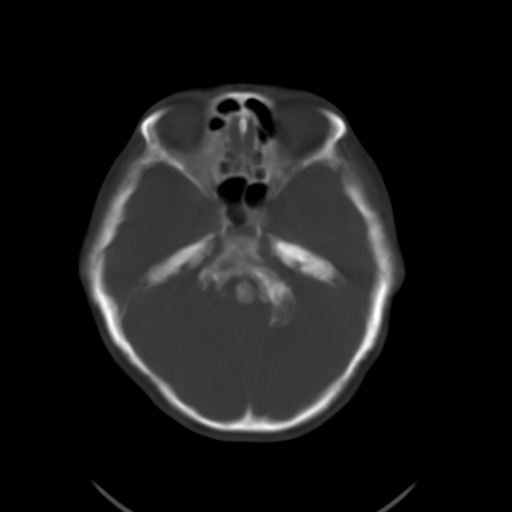

标题: CL0976:颅骨凹陷征 [打印本页]

标题: CL0976:颅骨凹陷征

女,56岁,头痛,没有其他的神经系统的阳性体征

颅底陷入是枕大孔周围骨,包括枕骨基底部、髁部和鳞部上升向颅腔内陷入的畸形。环、枢椎也随之上升、突入。多属枕骨及环枢椎先天性发育异常,也可继发于引起颅底软化的疾病、成骨不全或佝偻病等。

颅底凹陷症!这样横断位未见过,平时都是颈椎侧片所示。建议颈椎mr检查。

颅底凹陷.典型.